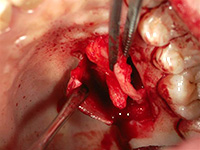

結合組織移植術

右上3番、4番の歯の根が露出していたため、上顎の裏側から結合組織を移植しました。

上顎裏側の結合組織を摘出しています。術後の傷も、きれいに治りました。